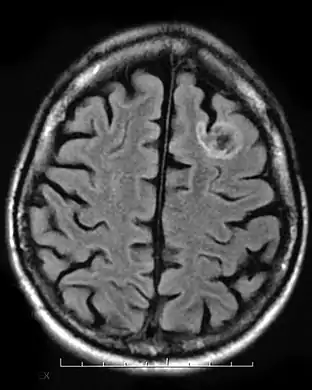

A dysembryoplastic neuroepithelial tumour is commonly diagnosed in patients who are experiencing seizures with magnetic resonance imaging (MRI), electroencephalogram (EEG).[4] A DNT is most commonly diagnosed in children who are experiencing seizures, and when given medication do not respond to them. When an MRI is taken there are lesions located in the temporal parietal region of the brain.[4]

Typical DNTs can be detected in an EEG scan when there are rapid repetitive spikes against a contrasted background.[4] EEG are predominantly localized with DNT location in the brain, however there are nonspecific cases in which the location of the tumour is abnormal and not localized.[4]